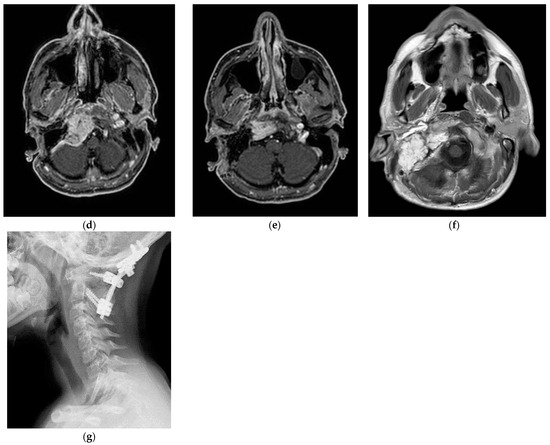

5.1. Case 1: (C4Di2)

| 1 | 25 | M | L | IX, X, XI, and XII | C4Di2 | 3 | Stent of left ICA + PBO |

| - | Total | 224 |

| 2 | 40 | M | R | IX, X, XI, and XII | C3Di1 + vagal | 1 surgery for CB PGL (left side) | Left ICA closed in another surgery and embolization involving stent of right ICA |

| - | Total | 95 |

| 3 | 32 | F | R | VI | C4Di2Vi | - | Absence of contralateral compensation and embolization involving stent of right-ICA |

| IX, X, and XII | Total | 336 |